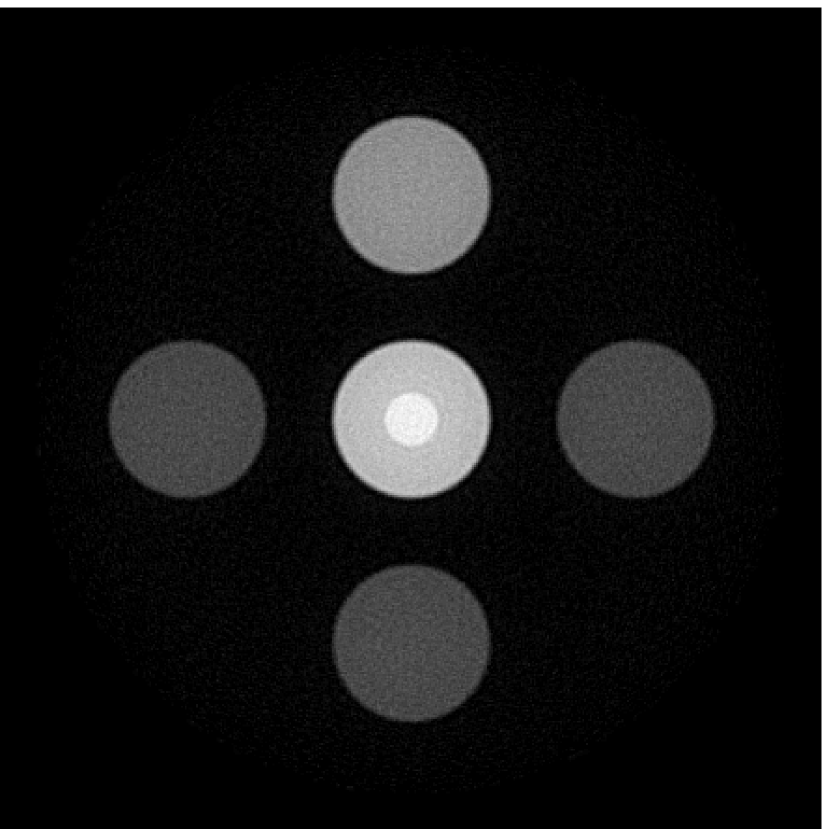

V-A4 Effect of initial estimate of EIR

As shown in Figure 6, when the error in the EIR was small (e.g., as with the EIR in Figure 6(a)), images were reconstructed with high accuracy using the VP algorithm. When the perturbations in the EIR were stronger (e.g, as in Figure 6(c)), artifacts and distortions in the reconstructed images were still significantly reduced by use of the VP algorithm; however, larger values of the regularization parameters had to be applied. When as in the initial EIR in Figure 6(e), no improvement was observed in the image reconstructed by use of the VP algorithm.